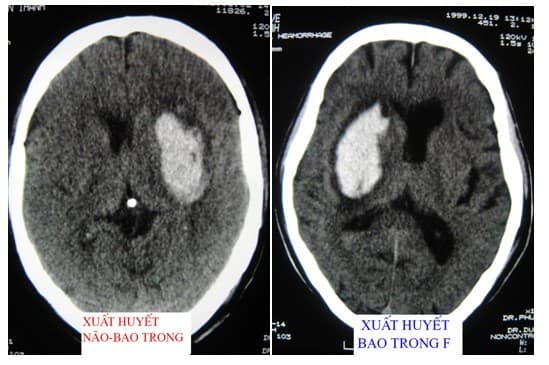

Trước khi có chỉ định điều trị, bác sĩ sẽ xác định phần nào của não bị tổn thương và dựa vào những triệu chứng để đưa ra phương pháp điều trị hiệu quả. Để biết chính xác bệnh thì bác sỹ có thể yêu cầu xét nghiệm hình ảnh bằng cách chụp cộng hưởng từ để phát hiện được xuất huyết nôi hay tụ máu. Ngoài ra, phương pháp khám thần kinh hoặc khám mặt cũng có thể được áp dụng để phát hiện dây thần kinh có bị phù không.